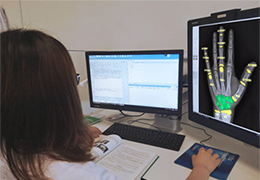

ANYTHINK 经导管主动脉瓣膜置换术分析系统